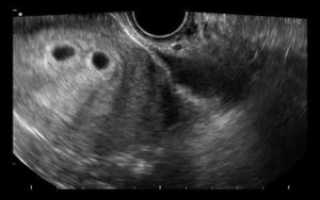

Фото беременности двойней на ранних сроках, 12 недель

В 12 — 14 недель все беременные проходят первый скрининг. Женщин, ожидающих двойню или тройню, отправляют на исследования как можно раньше. На 10-11 акушерской неделе.

УЗИ проводят скрининговым методом. То есть аппарат водят по животу, чтобы не повредить зародыши. На этом сроке уже видно количество плацент и плодных пузырей.